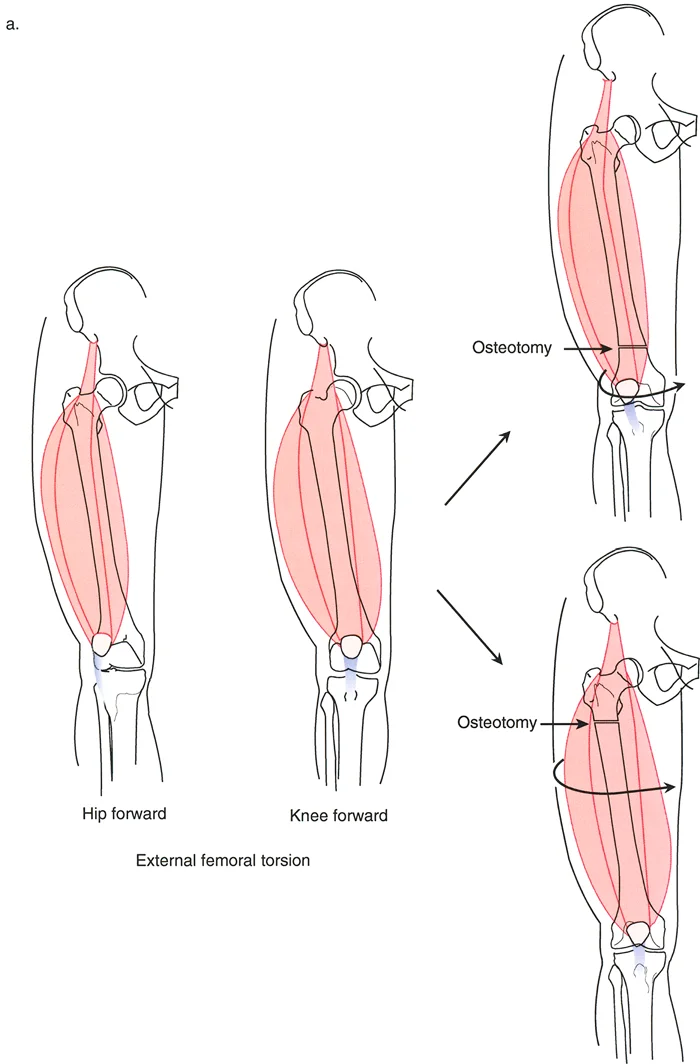

* تشوه الدوران: يعني أن العظم ملتف حول محوره الطولي، مثل لوي قطعة قماش. قد يكون الفخذ ملتفاً للداخل أو للخارج، أو قصبة الساق ملتفة، مما يجعل القدم تتجه للداخل أو للخارج بشكل غير طبيعي عند المشي.

غالباً ما تتواجد هذه التشوهات معاً، مما يجعل الحالة أكثر تعقيداً. فمثلاً، قد يكون عظم الفخذ منحنيًا وفي نفس الوقت ملتفاً. هذا التداخل يخلق "تشوهاً ثلاثي الأبعاد" يتطلب فهماً عميقاً وكفاءة عالية لتصحيحه.

عندما يكون العظم مشوهاً في كل من الانحراف الزاوي والدوران، فإن أي محاولة لتصحيح أحد الجانبين دون الآخر قد تؤدي إلى نتائج عكسية أو حتى مضاعفات خطيرة. على سبيل المثال:

* إذا قمت بتصحيح الانحناء فقط وتجاهلت الدوران، فقد يظل المريض يعاني من مشكلة في المشي أو ألم في الركبة.

* إذا تم تصحيح الدوران بشكل خاطئ أو في مستوى غير صحيح، فقد يؤثر ذلك على عمل العضلات المحيطة، خاصة عضلات الفخذ الأمامية (الرباعية)، مما قد يؤدي إلى خلع صابونة الركبة أو تآكل غضروف الركبة (تلين الغضاريف).

تحديد مستوى التشوه بدقة

إن تحديد المستوى الدقيق للتشوه الدوراني هو أحد أهم الخطوات في التخطيط الجراحي. على الرغم من أن الدوران هو تشوه زاوي في المستوى المستعرض، إلا أن موقعه على طول العظم (قريب من المفصل أو بعيد عنه) يؤثر بشكل كبير على كيفية تصحيحه وتأثيره على الأنسجة المحيطة.

- في الحالات الخلقية أو التنموية: يتطلب تحديد مستوى التشوه استنتاجاً سريرياً دقيقاً يعتمد على تأثيره العميق على مسار العضلات والأوتار. يعتمد الدكتور هطيف على خبرته الواسعة في تقييم هذه الحالات لتحديد المستوى الأمثل لقطع العظم.